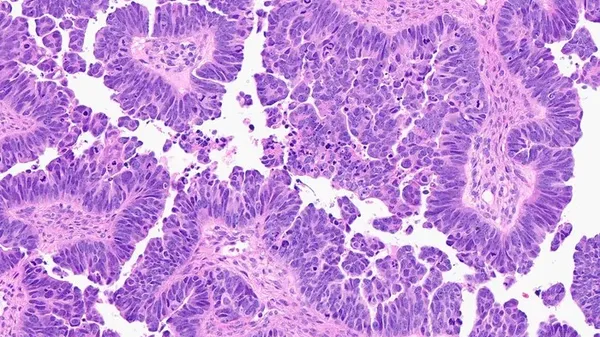

Correggere una cellula tumorale cercando i giusti ingredienti molecolari da combinare, come farebbe uno chef con una nuova ricetta: è l'innovativo metodo per la ricerca di farmaci antitumorali pubblicato sulla rivista Nature Biomedical Engineering dal gruppo di ricerca guidato da …